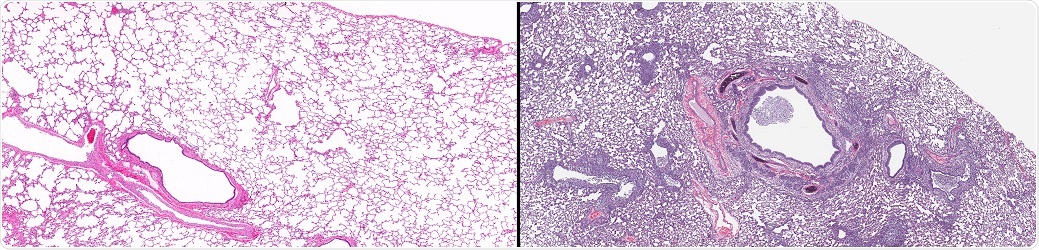

%26Lung_with_Influenza_(right)from_a_case_of_influenza_showing_microscopic_disease_pathology_of_flu-vetpathologist-1000.jpg)

Normal Lung (left) and Lung with Influenza (right). Comparative twin images of normal healthy lung in contrast to lung from a case of influenza showing microscopic disease pathology of flu. © vetpathologist / Shutterstock.com.